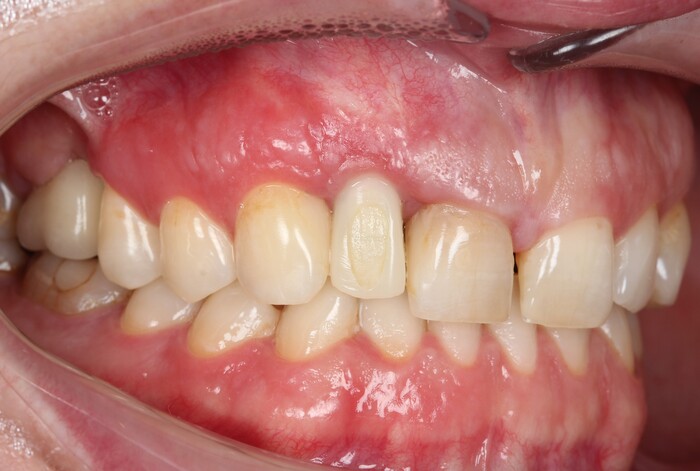

И вот картинка спустя полгода «ношения» новой временной коронки:

Я согласен, что эстетика хромает. Давно пора менять временную коронку на постоянную, что улучшит результат. Но, как я говорил, все упирается в финансы.

С другой стороны… с этого мы начали:

а на этом остановились: